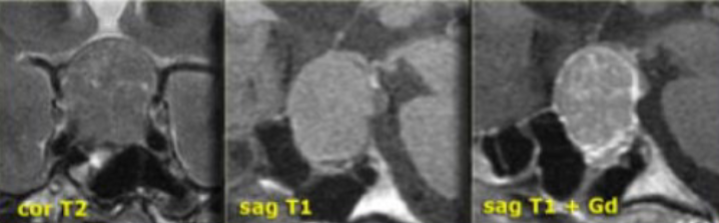

hyperostosis

no snowman on MRI

describe the appearance of a meningioma on imaging

meningioma

optic nerve sheath meningioma